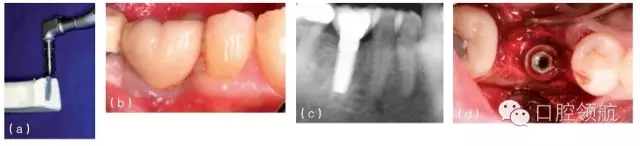

圖10.4 (a)在頜骨模型上,環(huán)鉆置于種植體上。環(huán)鉆是空心柱狀的,鉆的末端有切割螺紋。它放在種植體上,可以順著種植體邊緣周的骨組織的切線方向環(huán)行去除骨組織,從而使種植體移除造成的創(chuàng)傷減到最小。(b)種植單冠的頰面觀,種植修復(fù)后患者產(chǎn)生持續(xù)性的疼痛,且無法緩解,需要取出種植體。(c)根尖片顯示種植體正常。(d) 取出牙冠,翻瓣暴

露種植體。(e)用環(huán)形鉆取出包繞種植體的骨環(huán)。(f)環(huán)形鉆包繞種植體,環(huán)形切削達(dá)種植體全長(zhǎng)。(g)環(huán)形鉆切削完畢,(環(huán)形鉆中心的)切除的骨組織包繞種植體,種植體周圍已被分離,只有根尖區(qū)還有骨組織與種植體相連接。將使用一種器械,置于骨環(huán)周,切斷根尖區(qū)的骨組織。(h)包含種植體在內(nèi)的骨環(huán)被取出。(i)取出后置于外科盤上,可見種植體及附著周圍薄層的骨組織。種植體植入時(shí)曾植骨,種植體周可見殘留的顆粒狀的骨移植材料。(j)種植體移除后,去骨創(chuàng)面的牙合面觀。(k)將骨移植材料(同種異體骨與異種骨移植材料混合)放置在去骨創(chuàng)面中。(l)放上屏障膜,用釘固定。